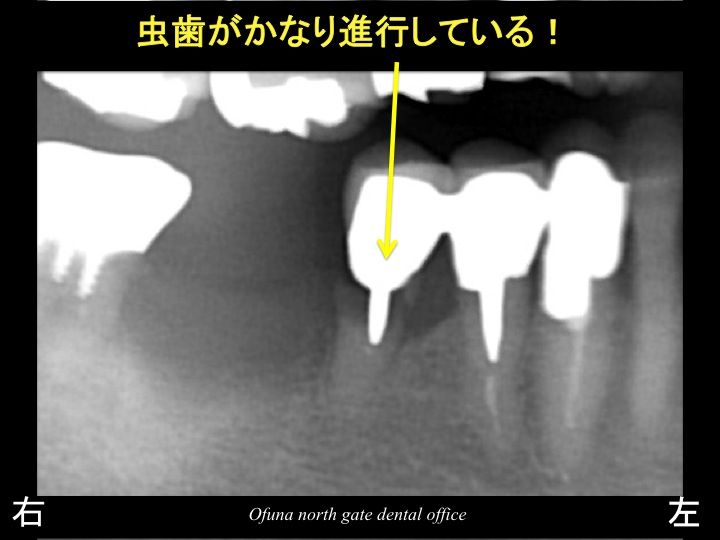

上記のレントゲン写真の丸で囲んだ部分を拡大したのが 以下になります。

欠損部(抜歯した歯の)手前の歯は、虫歯が非常に深く、

保存が厳しい状態です。

本来であれば、この虫歯の深い歯は、グラグラしても(取れても)おかしくない状態です。

しかし、この被せ物はグラグラして(取れていない)いません。

その理由として、手前の2歯と連結してあるのです。

つまり、3歯分連結した被せ物を装着してあるため、

虫歯が大きく進行していても 被せ物が取れたりすることがありませんでした。

また、この歯は神経がない歯です。

そのため、痛みもなく、患者様は問題をまったく感じていませんでした。

しかし、実際には 欠損部手前の歯は 保存が厳しい状態でした。

また、さらにその手前の歯も状態が悪い歯でした。